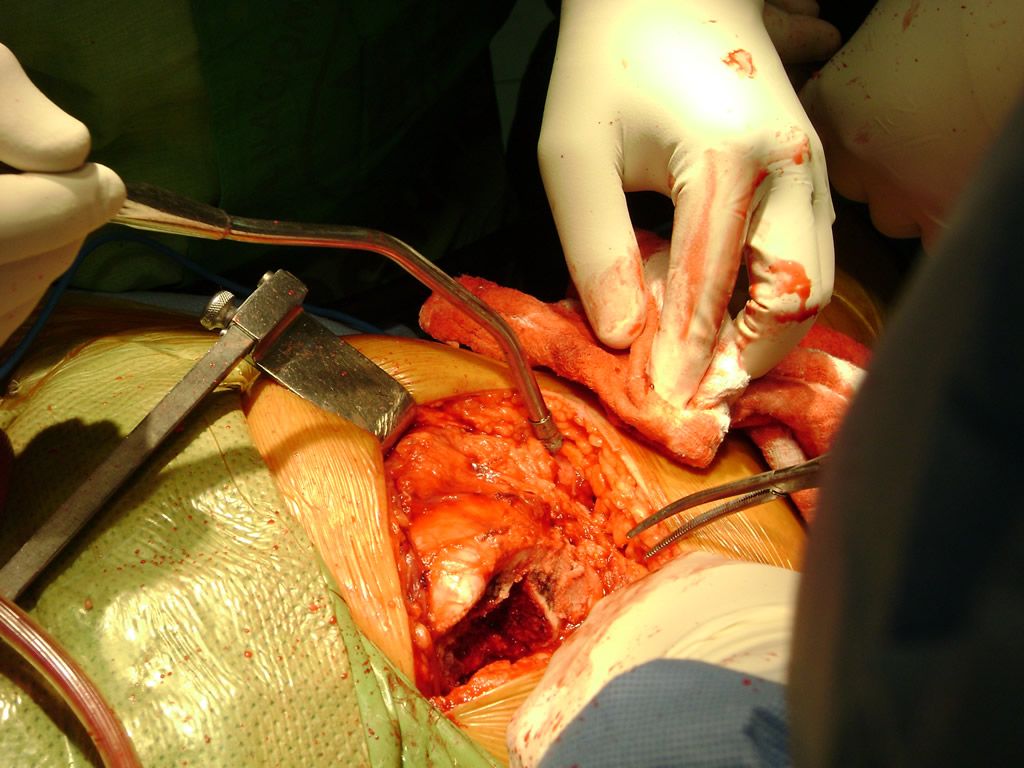

Aunque cada uno de estos huesos puede fracturarse por separado, normalmente la rotura es una lesión que se produce de forma conjunta

Debido a la fina cobertura de piel que recubre la tibia y el peroné, las fracturas generalmente son abiertas, es decir, el hueso roto rasga la piel, atravesándola. Las fracturas de tibia y peroné generalmente se producen por un fuerte impacto o torsión.